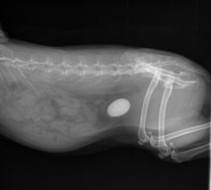

• badania: ultrasonograficzne - USG, cyfrowe RTG

• nowoczesny cyfrowy RTG

Diagnostyka obrazowa - USG, EKG, ECHO Doppler, RTG

Nasza Przychodnia wyposażona jest w wysokiej klasy aparat rentgenowski z cyfrowym skanerem zdjęć oraz aparat ultrasonograficzny do diagnostyki jamy brzusznej oraz badań echokardiograficznych serca z możliwością badań dopplerowskich.

Posiadany sprzęt pozwala nam na samodzielne wykonywanie wszystkich badań niezbędnych do oceny stanu narządów wewnętrznych naszych pacjentów.

Współpracujemy z renomowanymi radiologami w Polsce dzięki czemu możemy zagwarantować naszym Pacjentom profesjonalną diagnostykę z opisami radiologicznymi.

- obliczanie ilości płodów za pomocą RTG w trzecim trymestrze ciąży